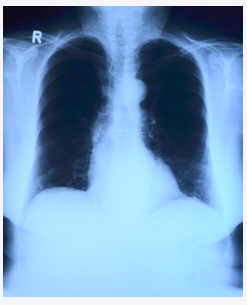

폐암은 한 마디로 폐에 생긴 악성 종양을 말하는데요. 폐 자체에서 암이 발병할 수도 있지만 다른 곳에 있던 암이 전이되어 폐에서 발전하는 경우도 있습니다.

현재까지 알려진 바에 의하면 폐암의 가장 큰 원인은 흡연으로 나타나 있습니다. 폐암 환자의 약 70%가 흡연으로 인해 발생한다고 하니, 흡연이 주된 원인 중 하나라고 할 수 있습니다.